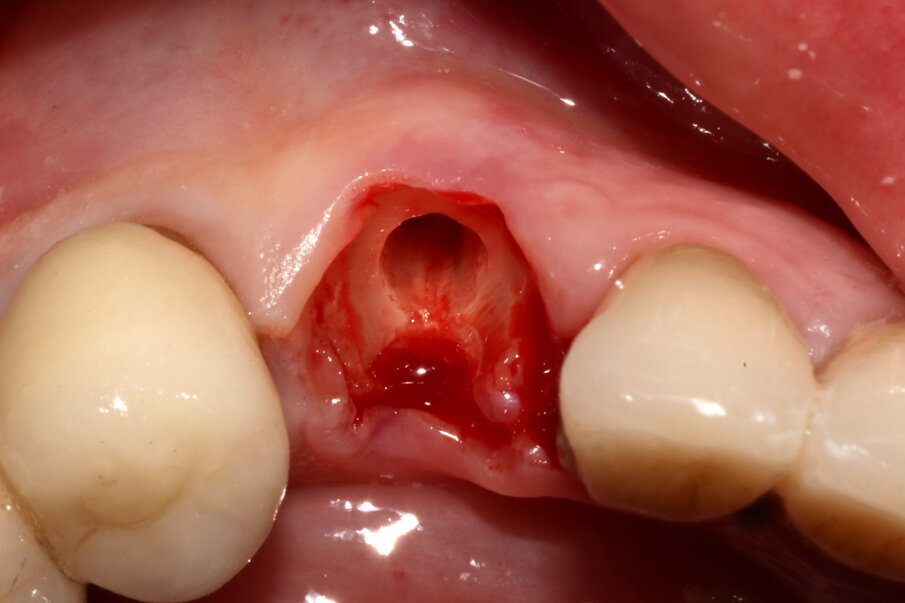

Il giorno della chirurgia, si procede all’intervento utilizzando il protocollo “Preserving

Nature” proposto dalla SISS (Figg. 5-7), che sostanzialmente prevede una decoronazione dell’elemento dentario e un trattamento della radice secondo una direzione crown-down: il canale viene svuotato, la radice raccordata al margine osseo vestibolare, e sezionata in modo da comprendere nella componente rimossa anche l’apice radicolare oltre che la porzione linguale della radice affetta da riassorbimento radicolare. Rimane così una piccola quota di radice vestibolare, spessa circa 1 mm e lunga circa 6 mm, con forma a “C” (per mantenere il legamento parodontale fino ai picchi ossei e mantenere così le papille interdentali). A questo punto viene inserito un impianto Nobel Active 4,3 x 13. Il controllo del posizionamento implantare in ossequio al progetto protesico viene eseguito grazie a un sistema di Chirurgia Navigata (X-Guide, X-Nav Technologies) che ci consente di ottenere una deviazione finale di soli 0,2° (Fig. 8). Una volta inserito l’impianto, lo stesso viene collegato a una torretta provvisoria in titanio sulla quale viene costruito un provvisorio intraoperatorio che rispetti il tragitto transmucoso e non eserciti forze compressive o dislocanti sullo shield vestibolare.

Figg. 5-7_Fasi della Socket-Shield: decoronazione, svuotamento del lume canalare e asportazione della porzione linguale della radice tramite protocollo “Preserving Nature”.